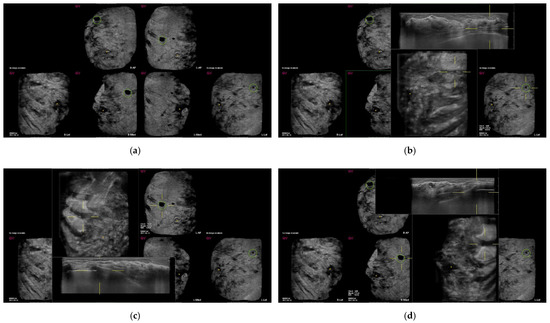

| False-positive marks for pseudolesions | 459 | 86 |

| Marginal shadowing | 209 | 39.1 |

| Cooper’s ligament shadowing | 143 | 26.8 |

| Periareolar shadowing | 64 | 12 |

| Rib | 37 | 6.9 |